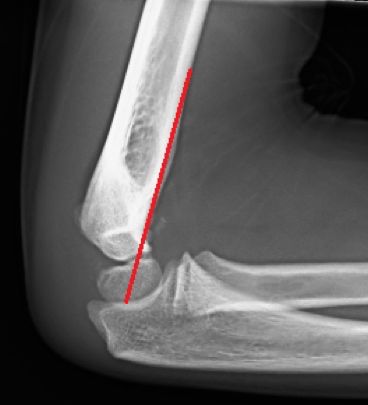

- Línea humeral anterior (LHA): La línea humeral anterior debe pasar por el centro del capitelum. Si el centro del capitelum es posterior a ésta línea, se debe sospechar una fractura supracondílea en extensión o una fractura transfisaria (más frecuente en niños muy pequeños). Si el capitelum es anterior a ésta línea, se debe sospechar una fractura supracondílea en flexión (menos frecuente) o una fractura transfisaria. Es primordial obtener una radiografía lateral pura del húmero distal, ya que la rotación, puede darnos falsas referencias haciendo que el capitelum aparezca posterior. (Figura 2)

Figura 2: a-La línea humeral anterior debe cortar al capitelum en su zona media. b- Fractura supracondílea en extensión donde la línea humeral anterior pasa por delante del capitelum.